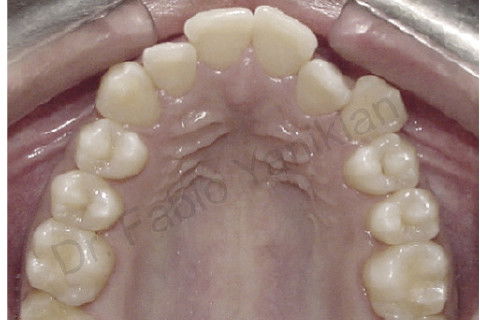

Foto oclusal superior inicial

Foto oclusal superior final

Paciente CL I com apinhamento superior e inferior

Evolução clínica: exo dos 4 prés, alinhamento e nivelamento, não foi necessario fazer RAS e RAI mas perda de ancoragem nos 4 quadrantes para fecar os espaços.